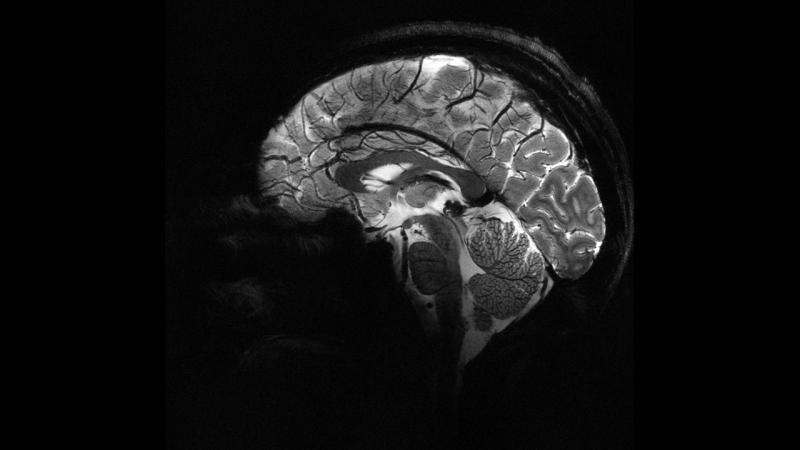

Французский научно-исследовательский институт Комиссариат по атомной и альтернативным видам энергии (Commissariat à l'énergie atomique et aux énergies alternatives, CEA) опубликовал самое четкое изображение человеческого мозга, полученное с помощью самого мощного в мире магнитно-резонансного томографа (МРТ).

Как заявили в CEA, снимок мозга, сделанный с помощью аппарата МРТ под названием Iseult, был получен в результате исследования, продолжавшегося более 20 лет.

В рамках исследований за последние несколько месяцев аппарат МРТ с магнитной силой 11,7 Теслабыл протестирован примерно на 20 здоровых добровольцах.

Благодаря аппарату, наиболее четкое изображение мозга удается получить почти за 4 минуты.

На получение таких же снимков с помощью обычных томографов, которые широко используются в больницах, понадобилось бы несколько часов, отметили французские ученые.